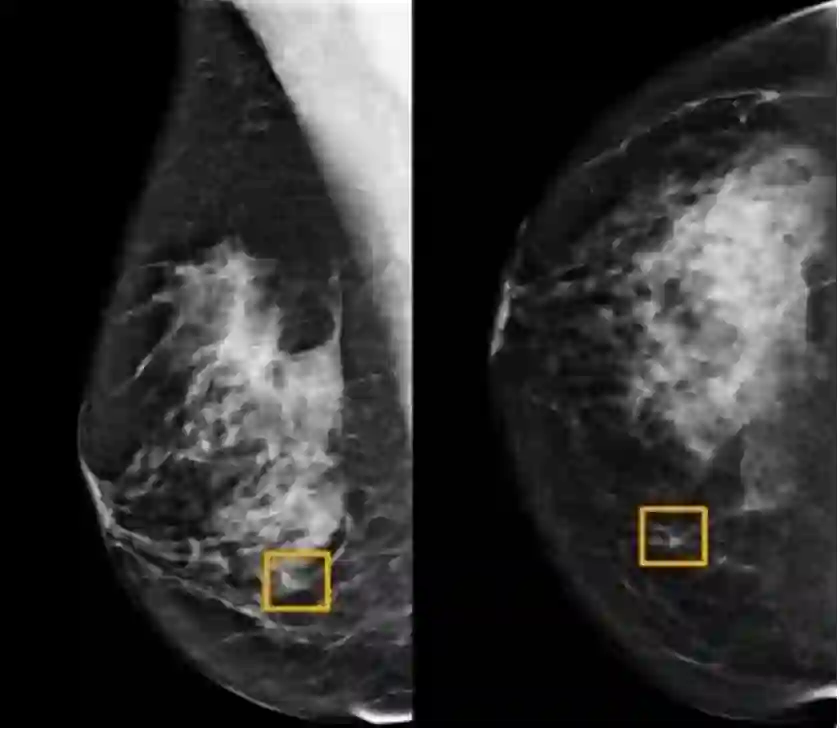

乳腺癌检测AI模型

而这款深度学习AI模型可以通过筛查乳房X光图像来检测乳腺癌。研究人员利用两个大型数据集对该系统进行了测评。结果显示:出现假阳性与假阴性的概率都下降了,其表现优于另一项研究中的放射科专家。

Screening mammography aims to identify breast cancer at earlier stages of the disease, when treatment can be more successful1. Despite the existence of screening programmes worldwide, the interpretation of mammograms is affected by high rates of false positives and false negatives2. Here we present an artificial intelligence (AI) system that is capable of surpassing human experts in breast cancer prediction. To assess its performance in the clinical setting, we curated a large representative dataset from the UK and a large enriched dataset from the USA. We show an absolute reduction of 5.7% and 1.2% (USA and UK) in false positives and 9.4% and 2.7% in false negatives. We provide evidence of the ability of the system to generalize from the UK to the USA. In an independent study of six radiologists, the AI system outperformed all of the human readers: the area under the receiver operating characteristic curve (AUC-ROC) for the AI system was greater than the AUC-ROC for the average radiologist by an absolute margin of 11.5%. We ran a simulation in which the AI system participated in the double-reading process that is used in the UK, and found that the AI system maintained non-inferior performance and reduced the workload of the second reader by 88%. This robust assessment of the AI system paves the way for clinical trials to improve the accuracy and efficiency of breast cancer screening.